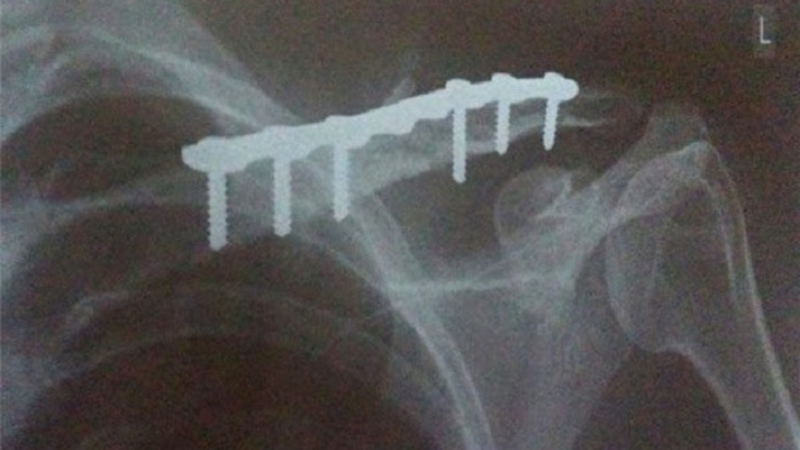

Khi nào thì nên cân nhắc rút đinh cố định sau chấn thương chỉnh hình? Tính chất sinh học của xương là mềm và dẻo dai. Trong khi đó, các đinh cố định và nẹp vít thường được làm từ thép không gỉ. Do sự khác biệt về tính chất này, đinh cố định chỉ hỗ trợ việc lành xương ở mức tương đối, không thể đảm bảo tính chắc chắn như mong đợi. Vì vậy, nếu có không tương thích giữa đinh cố định/nẹp với xương, có thể gây ra một số tác động phụ ảnh hưởng đến sức khỏe của bệnh nhân.